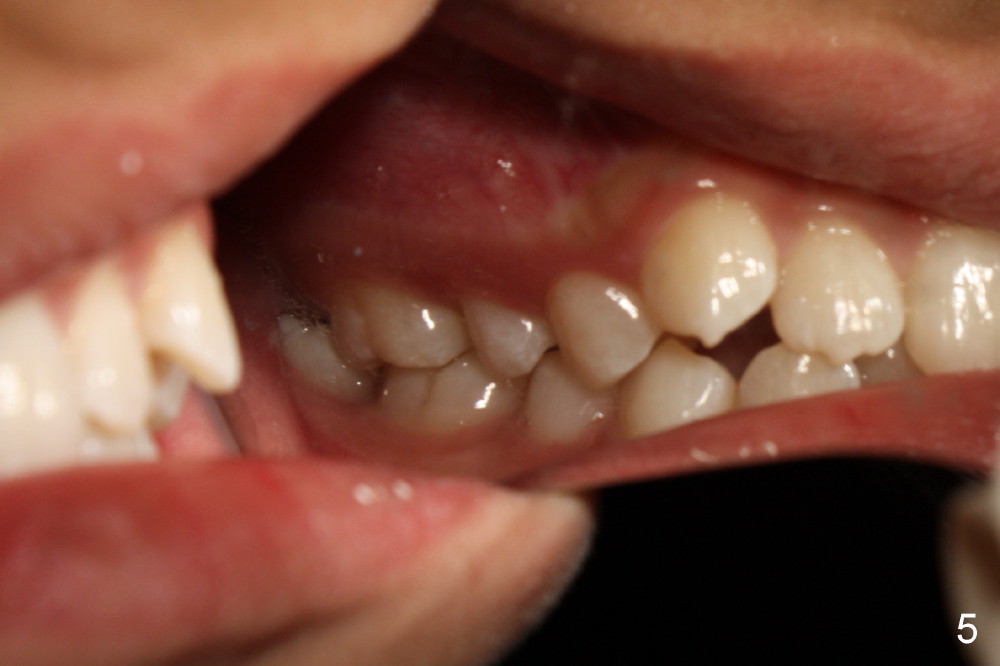

There is basically Class I occlusion in molar and canine regions bilaterally (Fig.3,5). Crowding is severe in the anterior area (Fig.4).